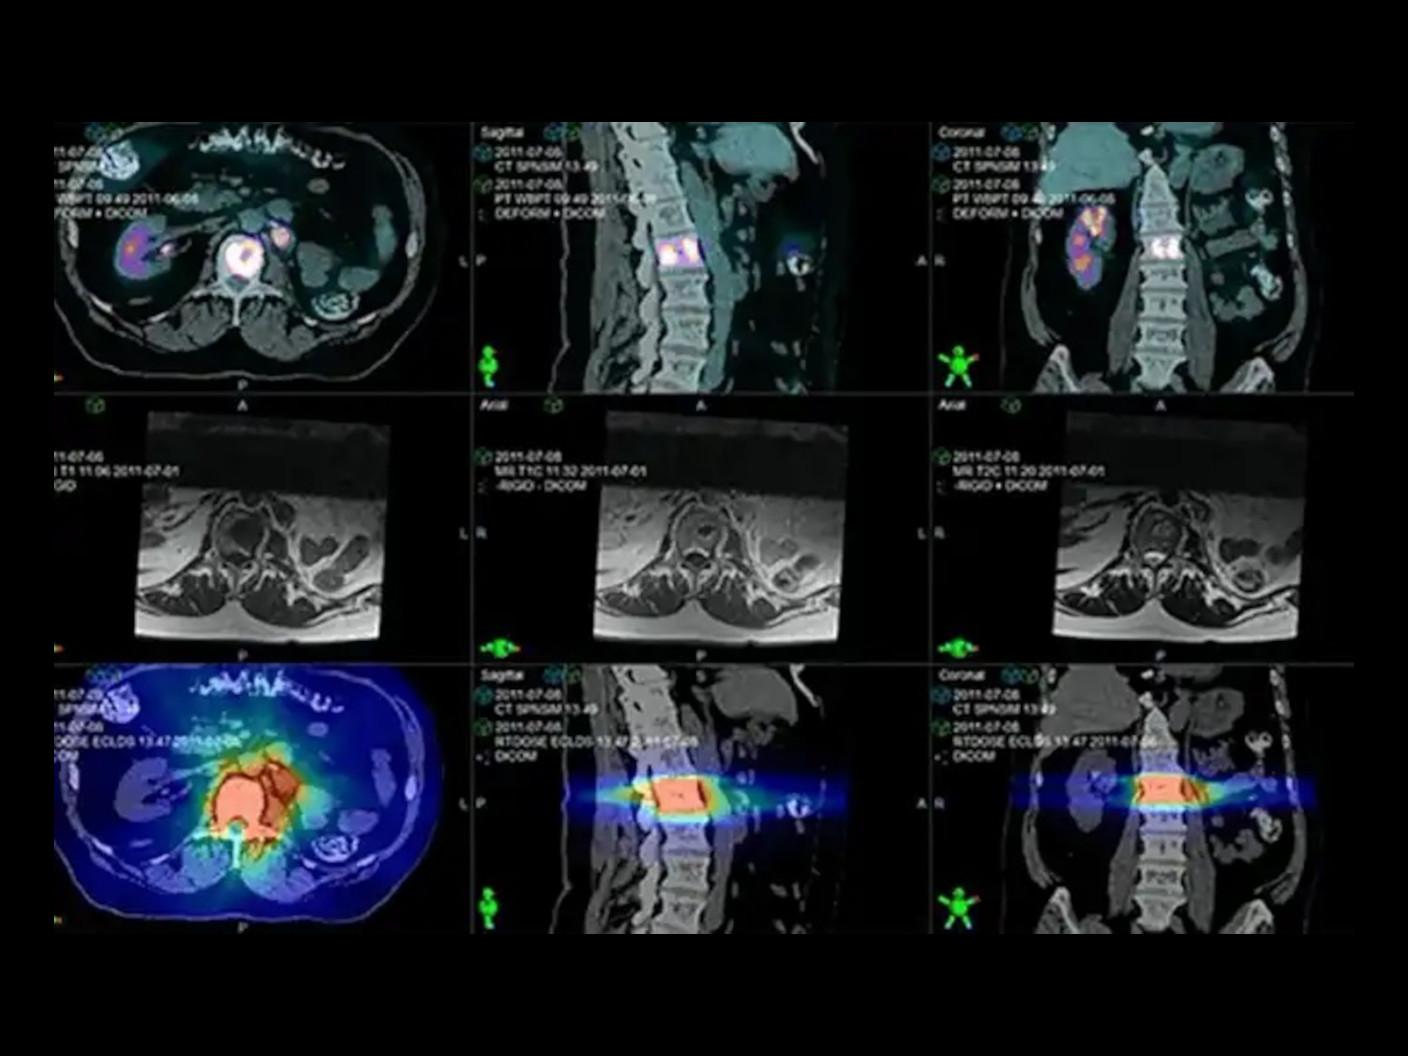

PET/CT for Radiation Therapy